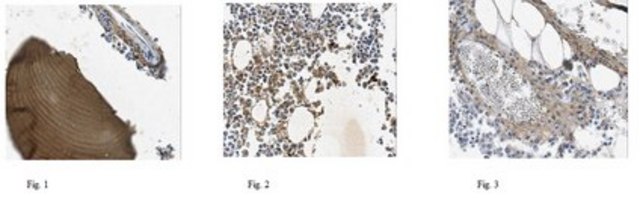

Evaluated by Immunohistochemistry Analysis in human bone tissues.

Immunohistochemistry Analysis: A 1:50 dilution of this antibody detected COL1A2 in human bone tissues.